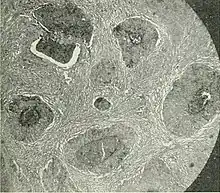

Barthlin carcinoma tissue cross section

Bartholin gland can be differentiated by histology to determine whether the malignancy is due to squamous cell carcinoma, adenoid cystic carcinoma, or adenocarcinomas.[5]